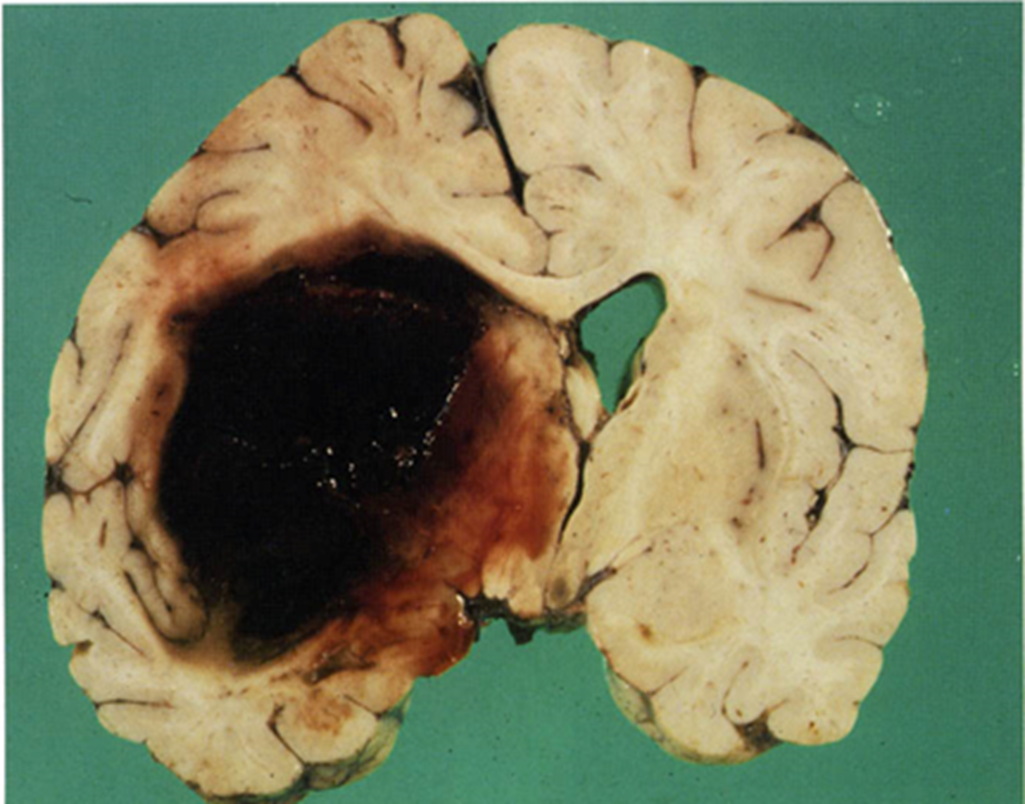

What are Intraparenchymal Hemorrhages

Intraparenchymal Hemorrhages result from rupture of vessels within the brain resulting in the formation of a hematoma

1) the resulting hematoma is walled off by brain tissue or it can rupture into a ventricle or subarachnoid space as an extension

→ forty percent of patients experience expansion of hematoma during the first 24 hours